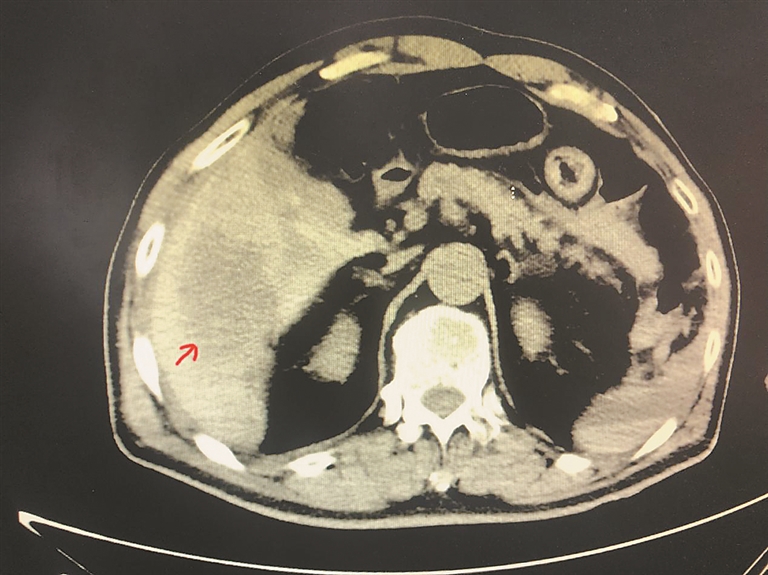

CT所示血管瘤的位置,大小约为9×7cm。

生活报讯 (记者王秋实) 家住哈市道外区的周先生已年过八旬,其肝右叶有一大血管瘤(直径约9cm),因有破裂大出血风险,医生建议手术切除。但周先生担心自己年龄大,又有脑梗,一直未选择手术治疗。近日,周先生在家中洗澡时不慎跌倒,右侧上腹剧烈疼痛,并伴有头晕,之后出现意识模糊,家人紧急叫120将其送到哈医大一院救治。